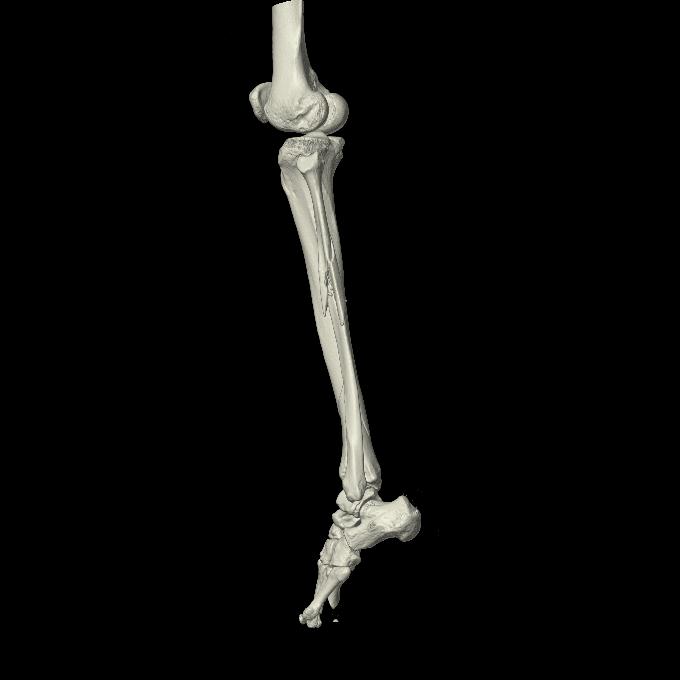

102803 1/12(キウスなし) 1/27 左下腿 4R 30歳女性 左脛骨軸内釘